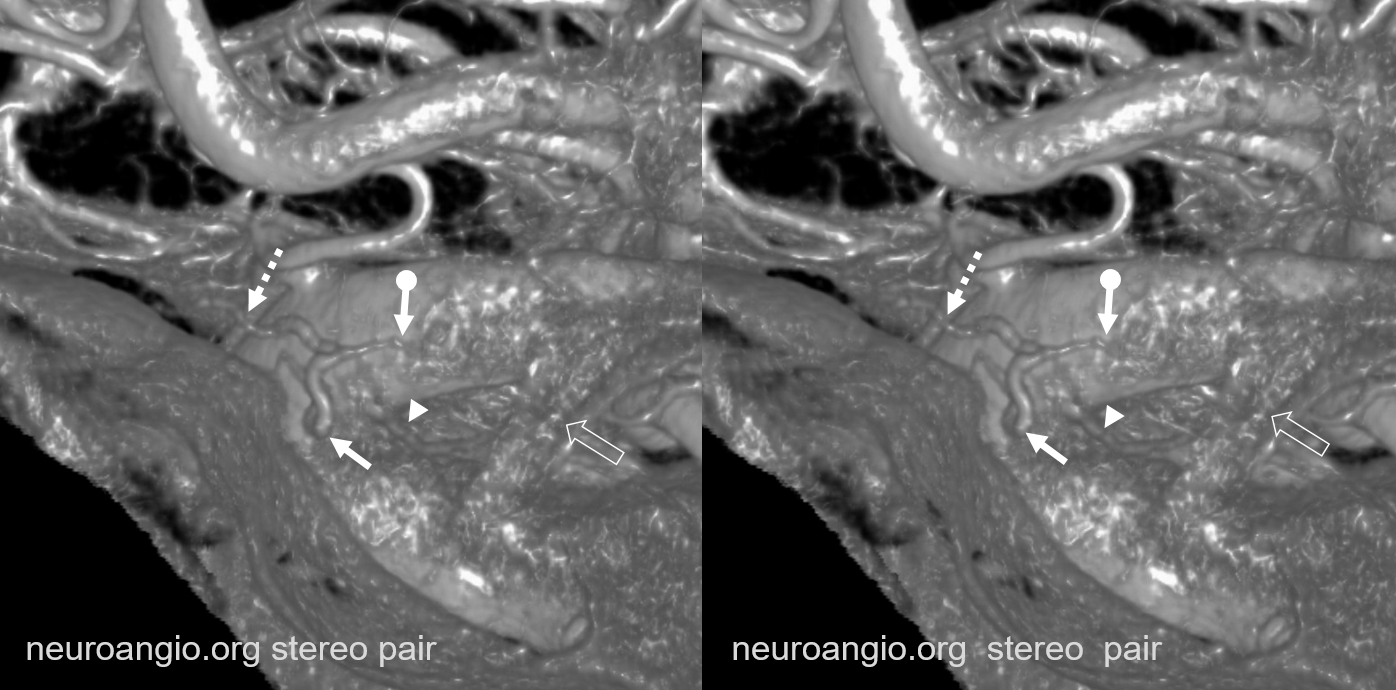

Supply of the Hypophysis and Balance

As always neuroangio is about balance. There may be one or more superior hypophyseal arteries. Usually one is visible by cone beam/flat panel CT. Sometimes more than two. Here there are 3. Nicely shown is supply of the stalk (open arrow). There is also likely contribution to the optic chiasm, which is of course very important. The inferior hypophyseal branches (dashed arrow) from the MHT support the posterior pituitary. The ILT is hypoplastic, with lateral branches of the MHT (white arrowhead) heading towards the meckel cave and the recurrent branch along the tentorial edge (black arrowhead) supplying territory normally done by the ILT

Without labels

More Optic Nerve Supply — its easier to see on MIPS, but with the right windowing, and stereo, VR imaging is also possible. Here, there are 3 superior hypophyseals seen. The anterior-most (arrow) is usually the largest, suppling the optic nerve (dashed arrow) and chiasm (ball arrow). The middle and posterior hypophyseals (arrowheads) supply the stalk.

Stereo of VR image. Same arrows. The stalk is open arrow.

Another patient — also 3 arteries. Cave origin of the anterior-most (arrows) one. The middle one (arrowheads) also supplies the optic nerve. The posterior one (dashed arrows) is for the stalk.

VR images (stereo pair on bottom). The cave origin of the anterior branch is most beautifully seen in the upper right image.